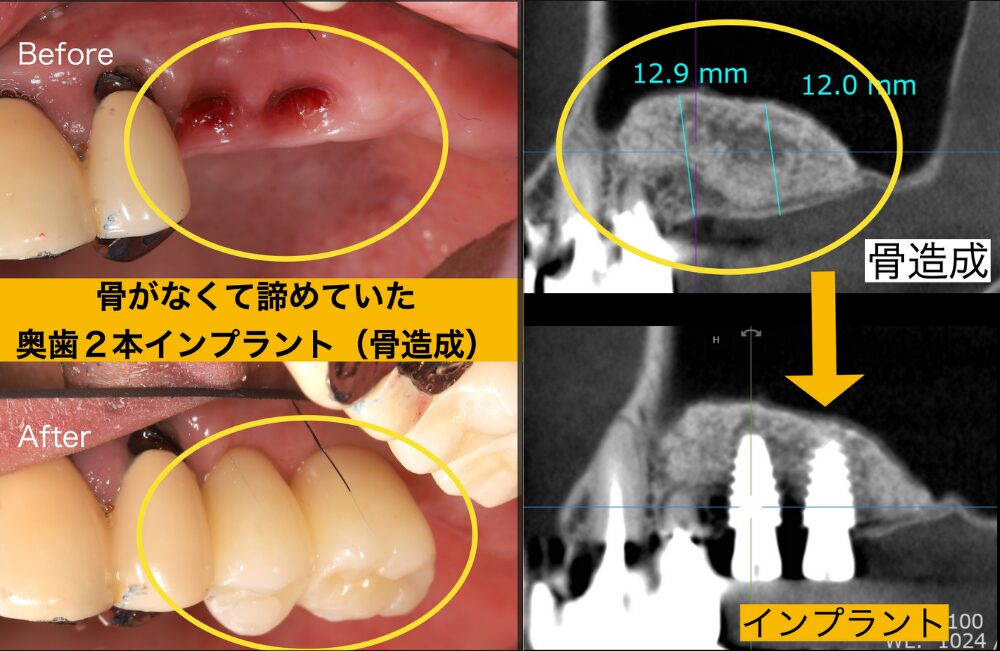

この患者様は30代の頃から下痢に悩まされていました。歯を失った理由は噛み合わせや歯並びが悪く歯ブラシもしにくいお口の環境でした。 奥歯を徐々に失い、年々噛めなくなり40代に入り胃腸の調子がますます悪くなってしまいました。

そこで意を決して治療に来られました。インプラントをするには骨が少なかったので骨造成を行い、無事にインプラントを入れることができました。

それからは奥歯でしっかりと噛めるようになったので、胃腸の調子も改善し体調がとても良くなったと喜ばれました。

骨がないと他院で言われて諦めていた患者様の体験談

骨がないからインプラントができないと言われている患者様が大勢いらっしゃいます。実はほとんどの場合、そんなことはありません。そう言われた方も決してあきらめないでください。

骨は無ければ造ることが可能です。そして、最近では骨が無くてもインプラント治療が可能な機器やシステムができてきました。

この患者様は1ミリほどしか骨が無くインプラントが難しいと言われていた患者様ですが、骨を12ミリほど造ることができ、問題なくインプラントを埋入することができました。骨が無くてもインプラントはできますので、別の医院でセカンドオピニオンを受けられることをおすすめします。